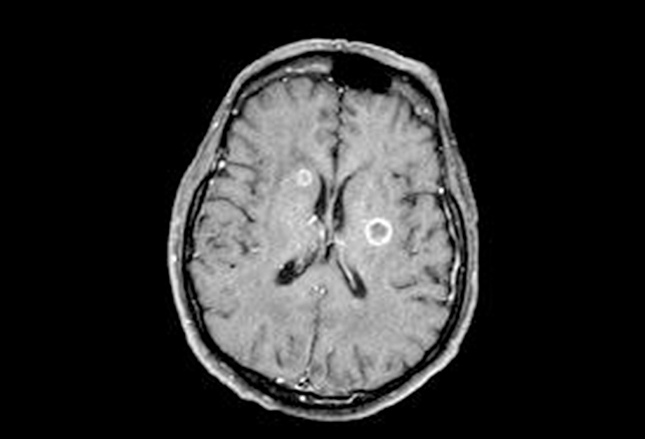

以上突变与NSCLC的相关性更加普遍。脑部是SCLC常见的扩散部位。上图为SCLC患者的脑部轴向对比剂增强MRI,室旁区可见两个环形强化病灶。